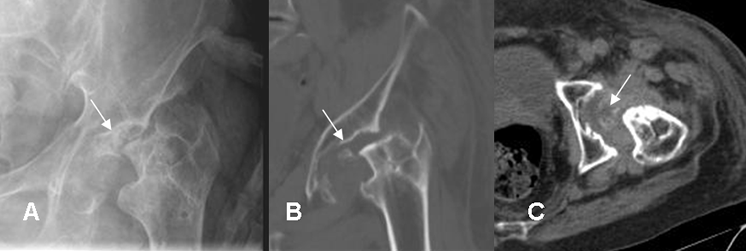

Fig 53 A. Artritis infecciosa.

A: Rx AP. Desplazamiento lateral del cojinete graso glúteo, que hace sospechar derrame articular. Lado derecho normal.

B: RM coronal y C: RM axial en STIR. Se confirma el derrame articular, por artritis infecciosa.

Fig 54. Artritis séptica.

A: Rx AP. Sin cambios significativos en el espacio. Hay pinzamiento mixto en la cadera.

B: RM coronal y C: RM axial en STIR. Derrame articular, por artritis infecciosa. En B hay cambios inflamatorios en la cavidad acetabular y en C en los músculos vecinos.